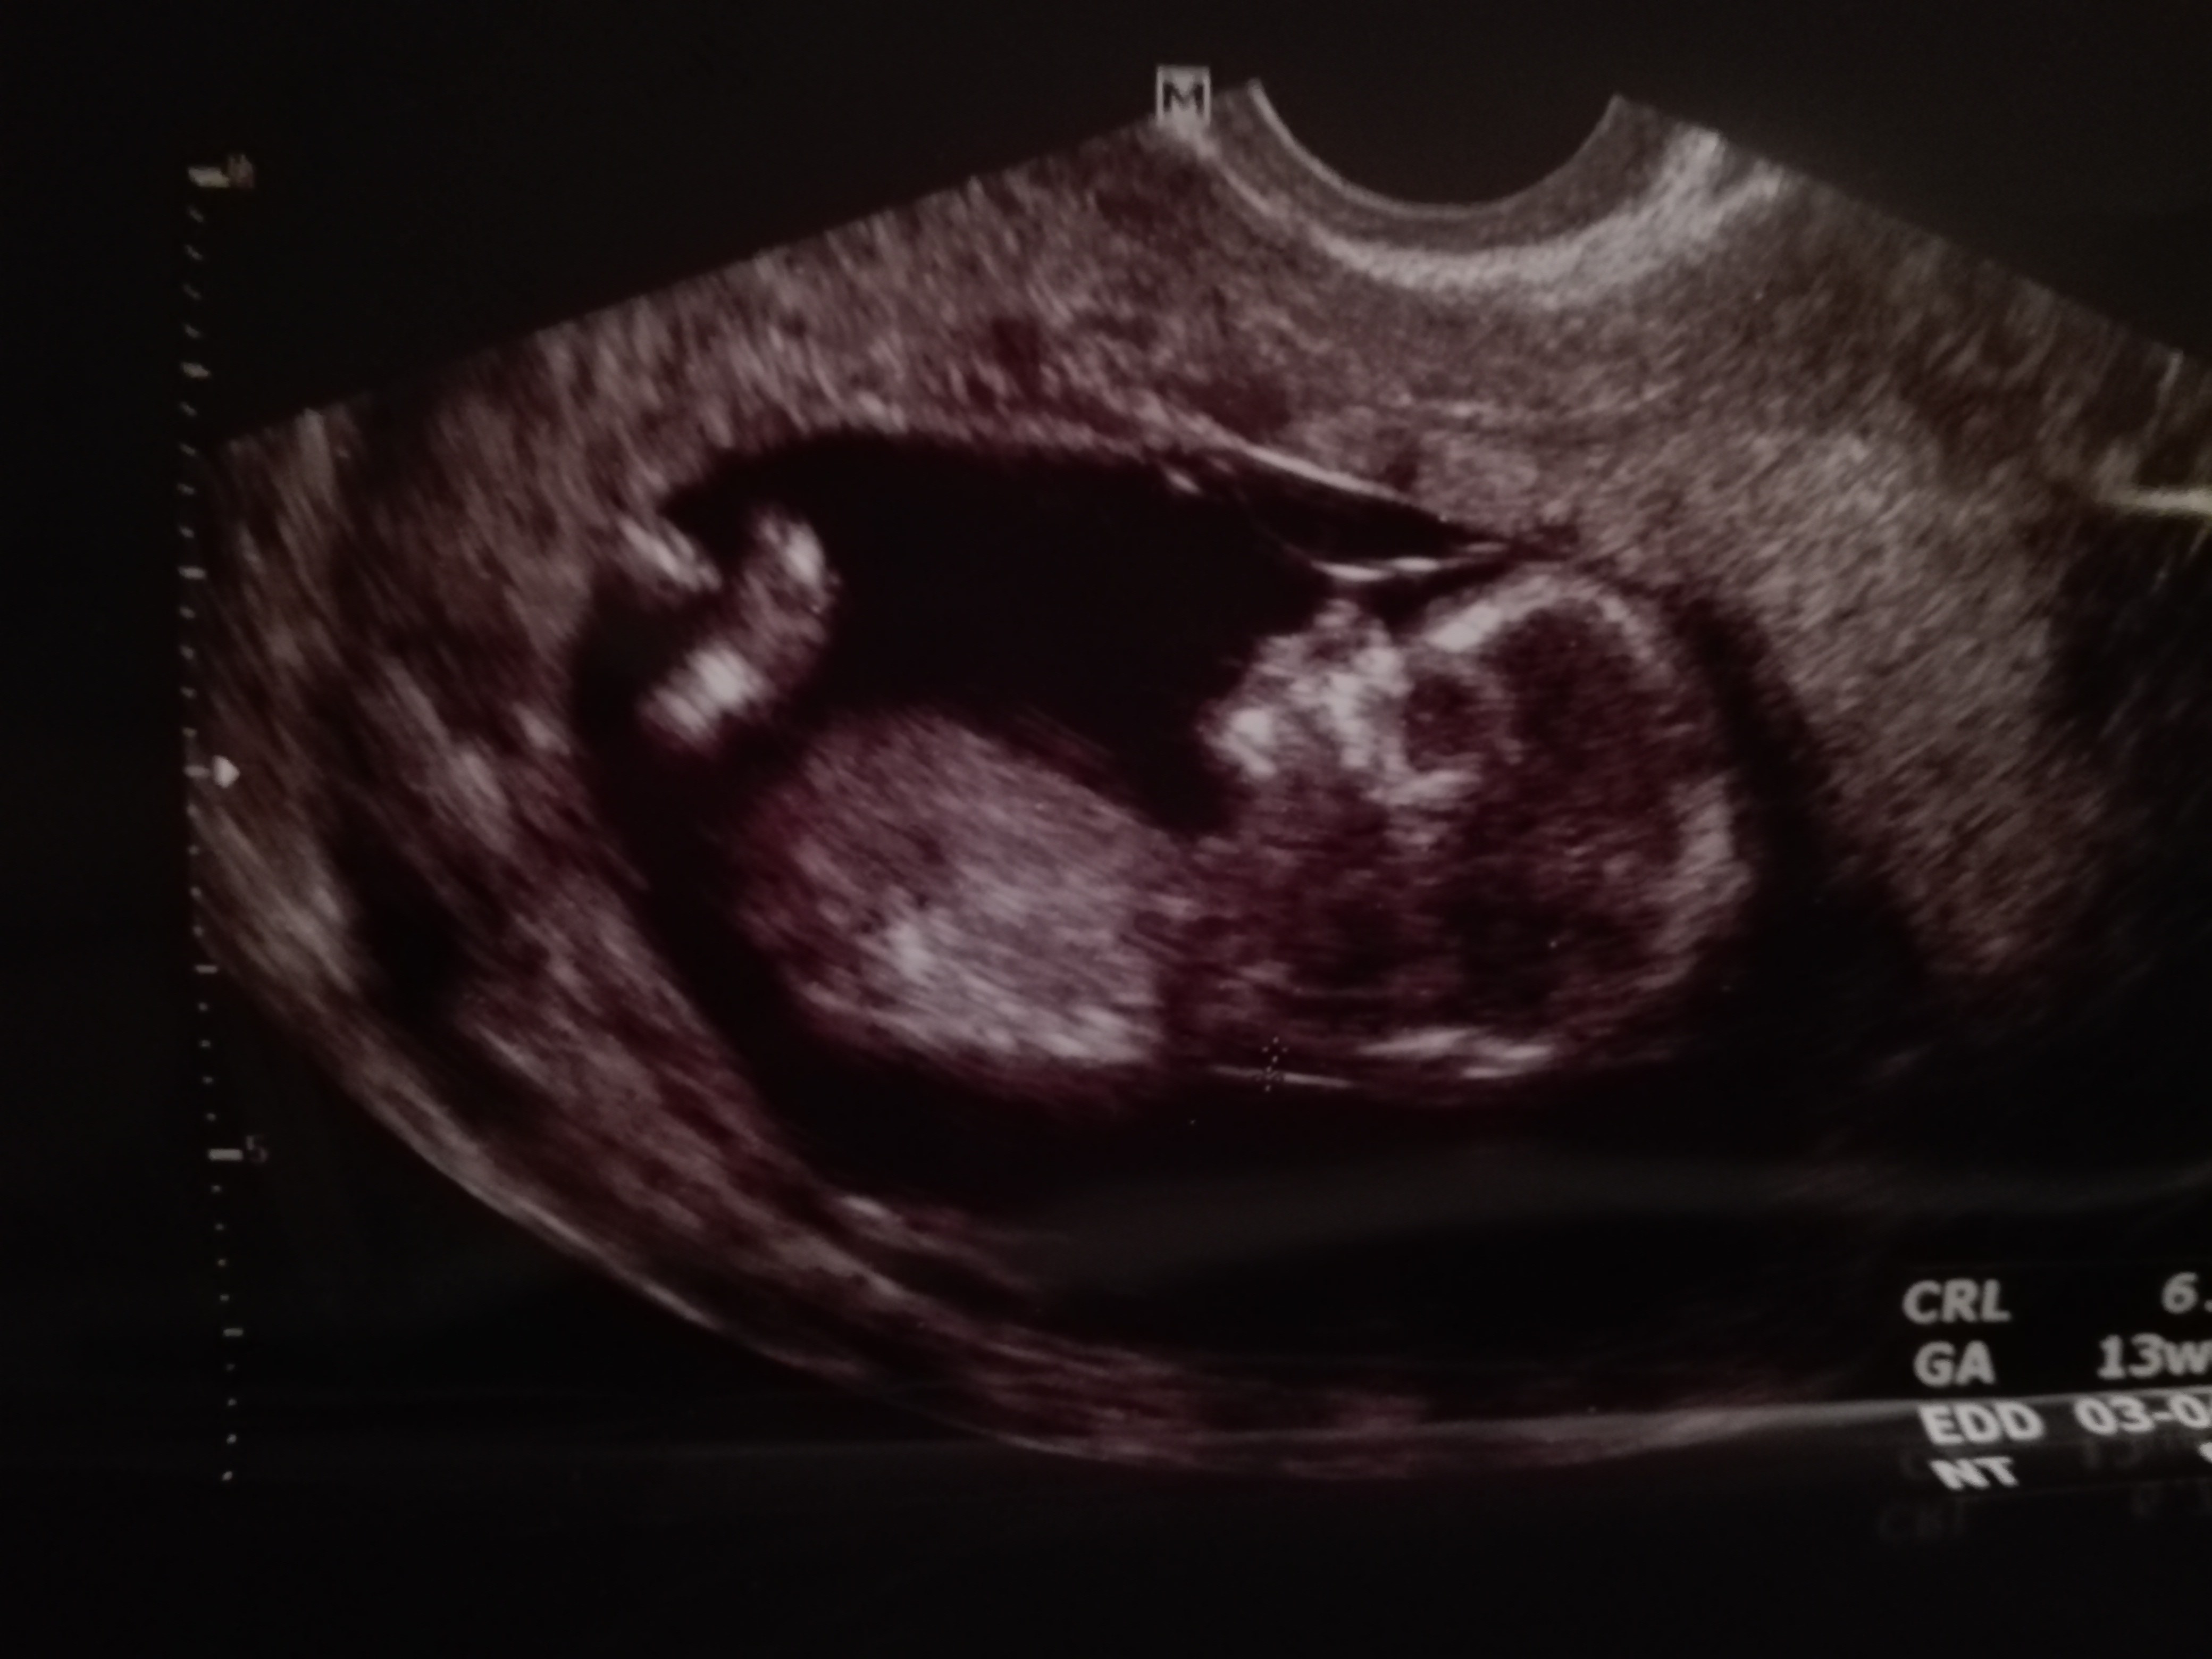

Badania prenatalne w 12 tygodniu, maleństwo 50,2mm, na USG lekarz stwierdził że nie widzi kości nosowej, przezierność karkowa 1,7mm, rączki, nóżki, serduszko w porządku. Po badaniu nie kazał się martwić bo może dziecko będzie miało po prostu mały nosek. Po 5 dniach przyszły wyniki badań USG+krew. HCG 1,309 Mom, Pappa 0,795MoM, brak kości nosowej - UWAGI: zwiększone ryzyko trisomii 21 - ryzyko podstawowe 1:479, ryzyko skorygowane 1:119. Zalecane wykonanie badań inwazyjnych, ale dopiero w 15-16 tygodniu

Nie wytrzymałabym tyle i tydzień później (w ten wtorek) zrobiłam test HARMONY oraz ponownie USG jest nosek, chrząstka, ale dalej nie widać kości nosowej. Teraz czas oczekiwania od 7-10 dni, tysiące myśli, zwariuje chyba przez ten czas